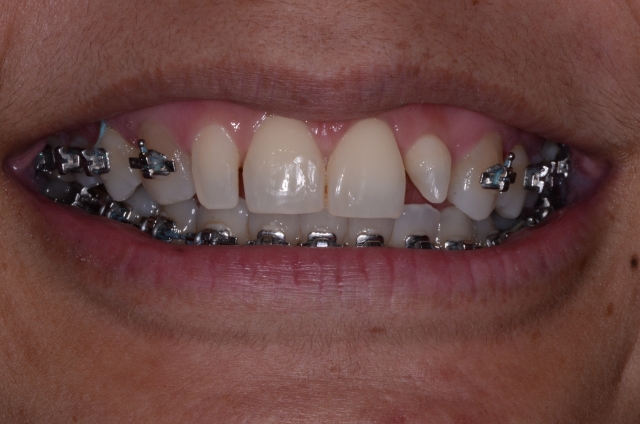

The good news is that if our patients really want the best solution and we do a good job of communicating with them, most of the time they[ll do the orthodontics. Once they’re committed, the first step is to have the orthodontist move the teeth into the proper position and then, if needed, take off the brackets (Fig. 7) so you can resize the teeth (Fig. 8).

One important thing to note is that these teeth have been resized but they’re still not aligned correctly because the bonding to resize them was done according to the root angulation and desired final size, not the current position. We don’t expect it to look perfect here — all we want is the right size and shape. We don’t care about alignment, and in fact, if the roots are still tipped, our bonding must follow that.